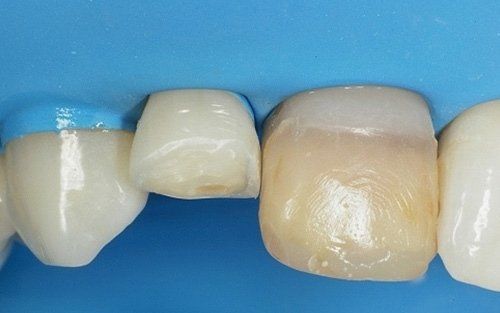

Qui raffigurato l'incisivo laterale di destra, dopo la rimozione del vecchio restauro.

Il restauro definitivo sul dente laterale: notare la buona integrazione fra il dente e il restauro.

Il laterale di sinistra dopo la rimozione del vecchio restauro. Anche in questo caso tutto il tessuto sano della paziente è stato mantenuto.

Il laterale di sinistra ultimato.